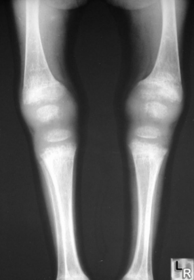

| What disease is this? What are the signs of this? | Osteogenesis imperfecta (“Brittle bone disease”) Diffuse cancellous osteopenia (coarse primary trabeculae), diminished tubular bone girth |

| What disease is this? | Rickets |

| What disease is this? | Osteogenesis Imperfecta |